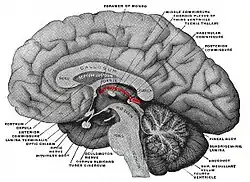

Stria medullaris highlighted in red over the thalamus. Posterior to the thalamus, the highlighted portion is the pineal gland | |